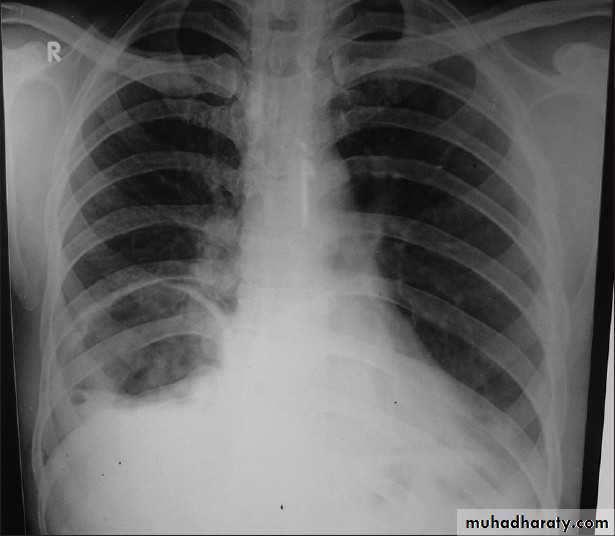

PneumothoraxX-ray pneumothorax

X-ray pneumothorax